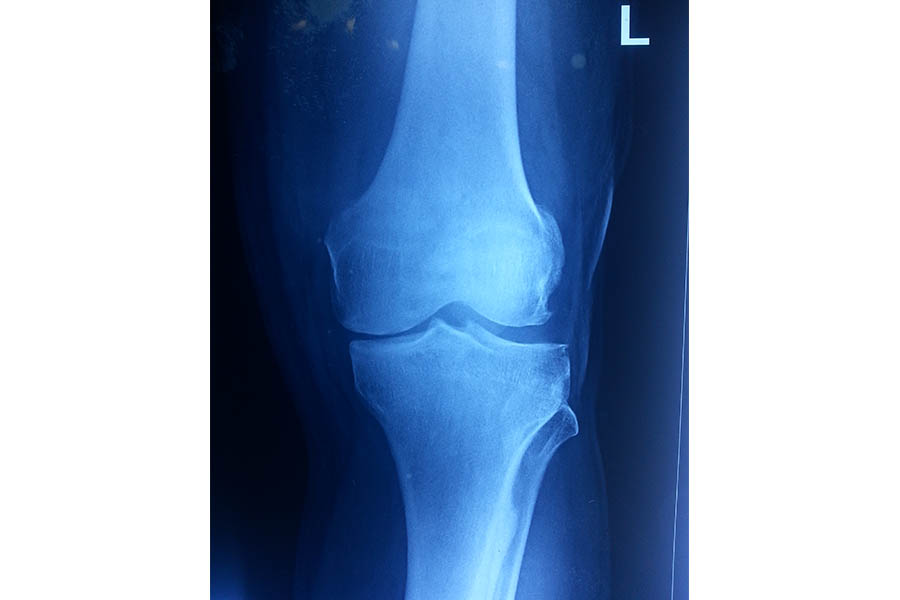

Trauma

Case 1